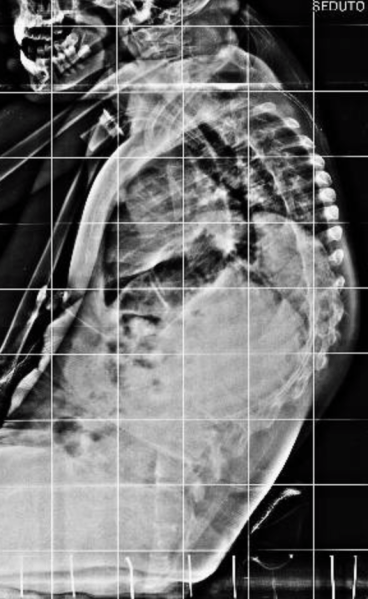

Qui di seguito, un esempio di un paziente affetto da scoliosi severissima, sottoposto a trattamento chirurgico.

Dopo l’intervento:

Schermata 2018-10-07 alle 22.30.15     Schermata 2018-10-07 alle 22.30.39